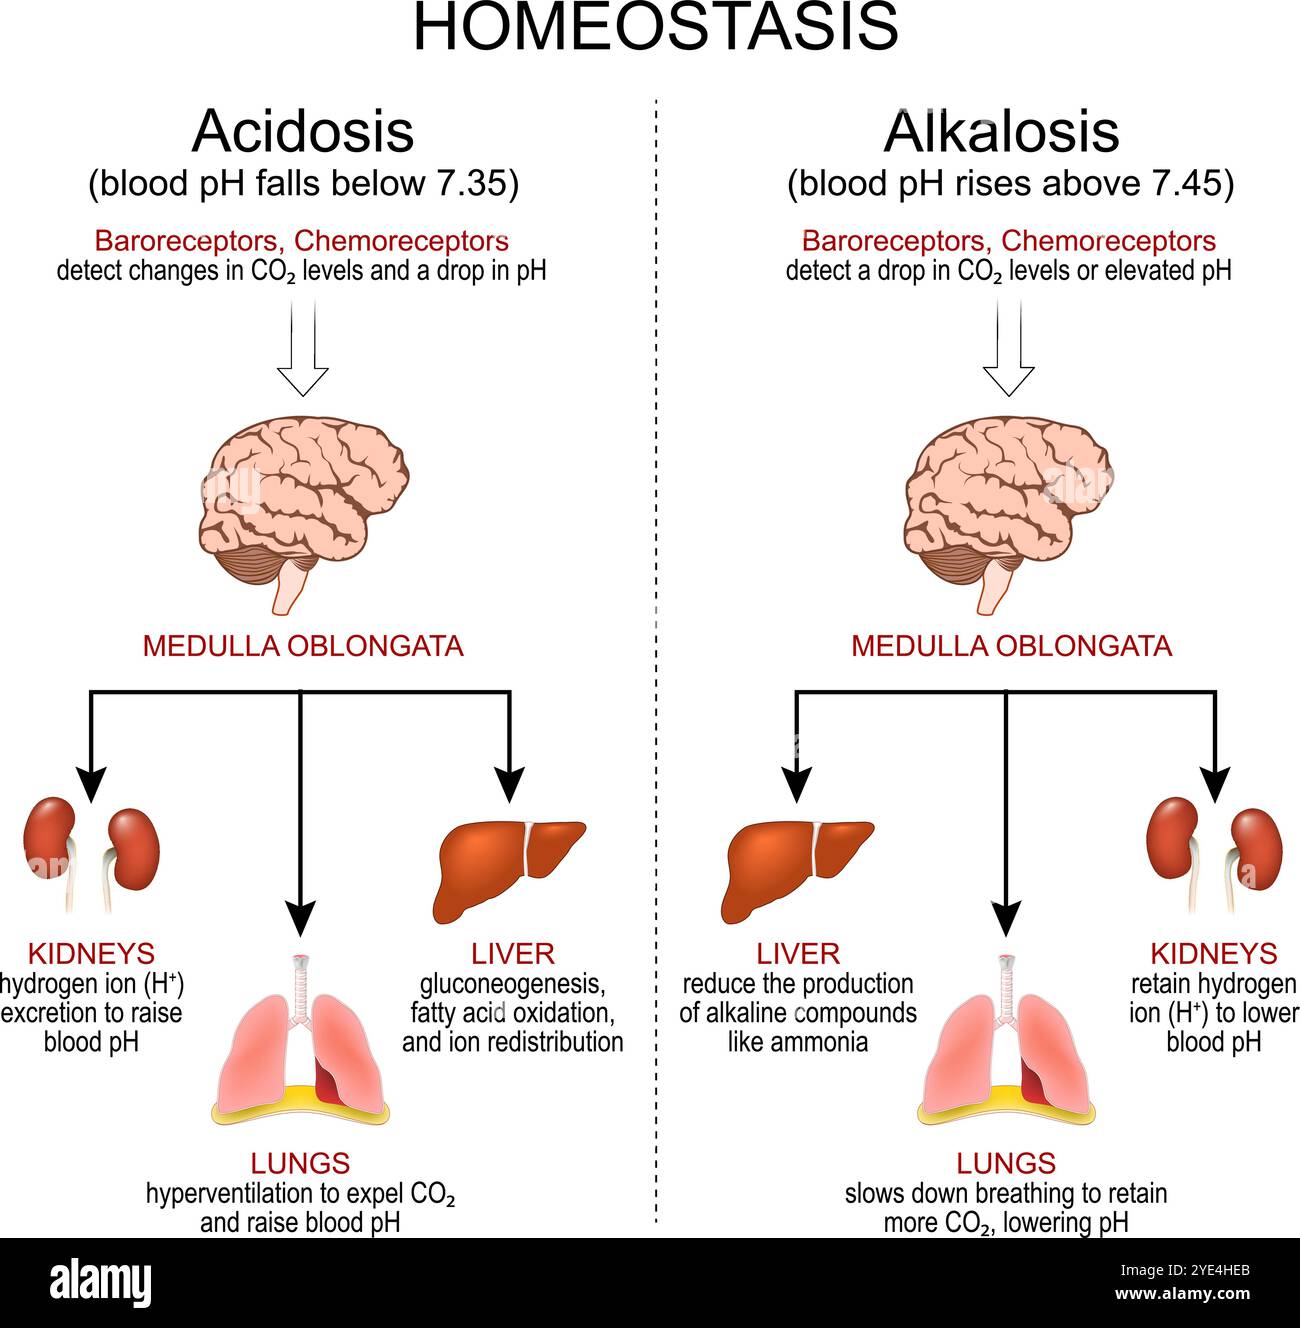

Homeostasis. pH regulation. Alkalosis, when blood pH rises above normal and Acidosis when blood pH falls below normal. Vector poster Stock Vectorhttps://www.alamy.com/image-license-details/?v=1https://www.alamy.com/homeostasis-ph-regulation-alkalosis-when-blood-ph-rises-above-normal-and-acidosis-when-blood-ph-falls-below-normal-vector-poster-image628279971.html

Homeostasis. pH regulation. Alkalosis, when blood pH rises above normal and Acidosis when blood pH falls below normal. Vector poster Stock Vectorhttps://www.alamy.com/image-license-details/?v=1https://www.alamy.com/homeostasis-ph-regulation-alkalosis-when-blood-ph-rises-above-normal-and-acidosis-when-blood-ph-falls-below-normal-vector-poster-image628279971.htmlRF2YE4HEB–Homeostasis. pH regulation. Alkalosis, when blood pH rises above normal and Acidosis when blood pH falls below normal. Vector poster